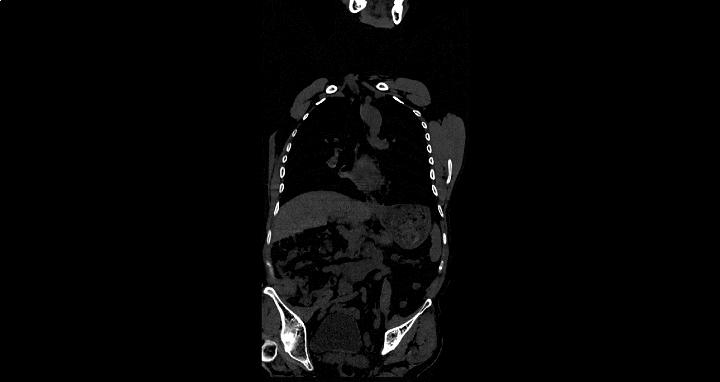

近日,经多方打听,她在丈夫的陪同下来到郑州市管城中医院骨伤科求医。郑州市管城中医院副院、骨伤科首席专家王长勇接待了刘女士,那天,年轻貌美却显憔悴的她,弯腰驼背、一瘸一拐地来到诊室。王院长检查她的 脊柱已处于僵直状态,无法平躺 ,完全不能直立靠墙, “4字试验”明显阳性,这时王院长心中已经有谱, 当即为她做腰椎MRI、骶髂关节MRI、炎症指标等相关检查。果然,不出所料,折磨她这么久的病根水落石出——强直性脊柱炎(“强直”)。

王院长说,强直性脊柱炎通过病史查体、CT/MRI、HLA-B27三个金标准容易明确诊断。虽然它给患者带来极大的痛苦和不便,但患上此病的患者朋友也无须惊慌。